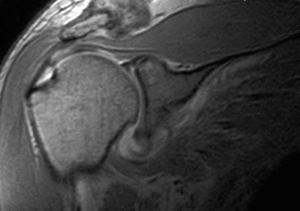

Tanto la cirugía abierta como la cirugía artroscópica son a menudo complementarias, pudiendo indicarse de forma correcta desbridamientos subacromiales artroscópicos, como cirugía paliativa en pacientes de mayor edad y con roturas masivas del manguito, así como realizar reparaciones tendinosas abiertas o asistidas con artroscopia en roturas pequeñas en pacientes en edad laboral y con requerimientos funcionales de mayor nivel. De hecho, los pacientes con mayor actividad laboral requieren una resolución de su síndrome doloroso y una recuperación completa de la función del hombro. En definitiva, en este grupo de pacientes, debe valorarse como tratamiento de elección la posibilidad de la cirugía abierta y reparadora del manguito rotador. Por el contrario, también en las roturas masivas del manguito, con afectación de más de un grupo muscular, con ascenso de la cabeza humeral, retracción mayor de 4 cm y degeneración grasa (fig. 4), la cirugía artroscópica, como gesto paliativo y descompresivo, por su baja morbilidad parece indicada en pacientes de edad avanzada, con dolor y con poca demanda funcional.

Figura 4. Estudios de imagen (RM y radiología simple) en rotura masiva de manguito rotador. Obliteración del espacio humeral.